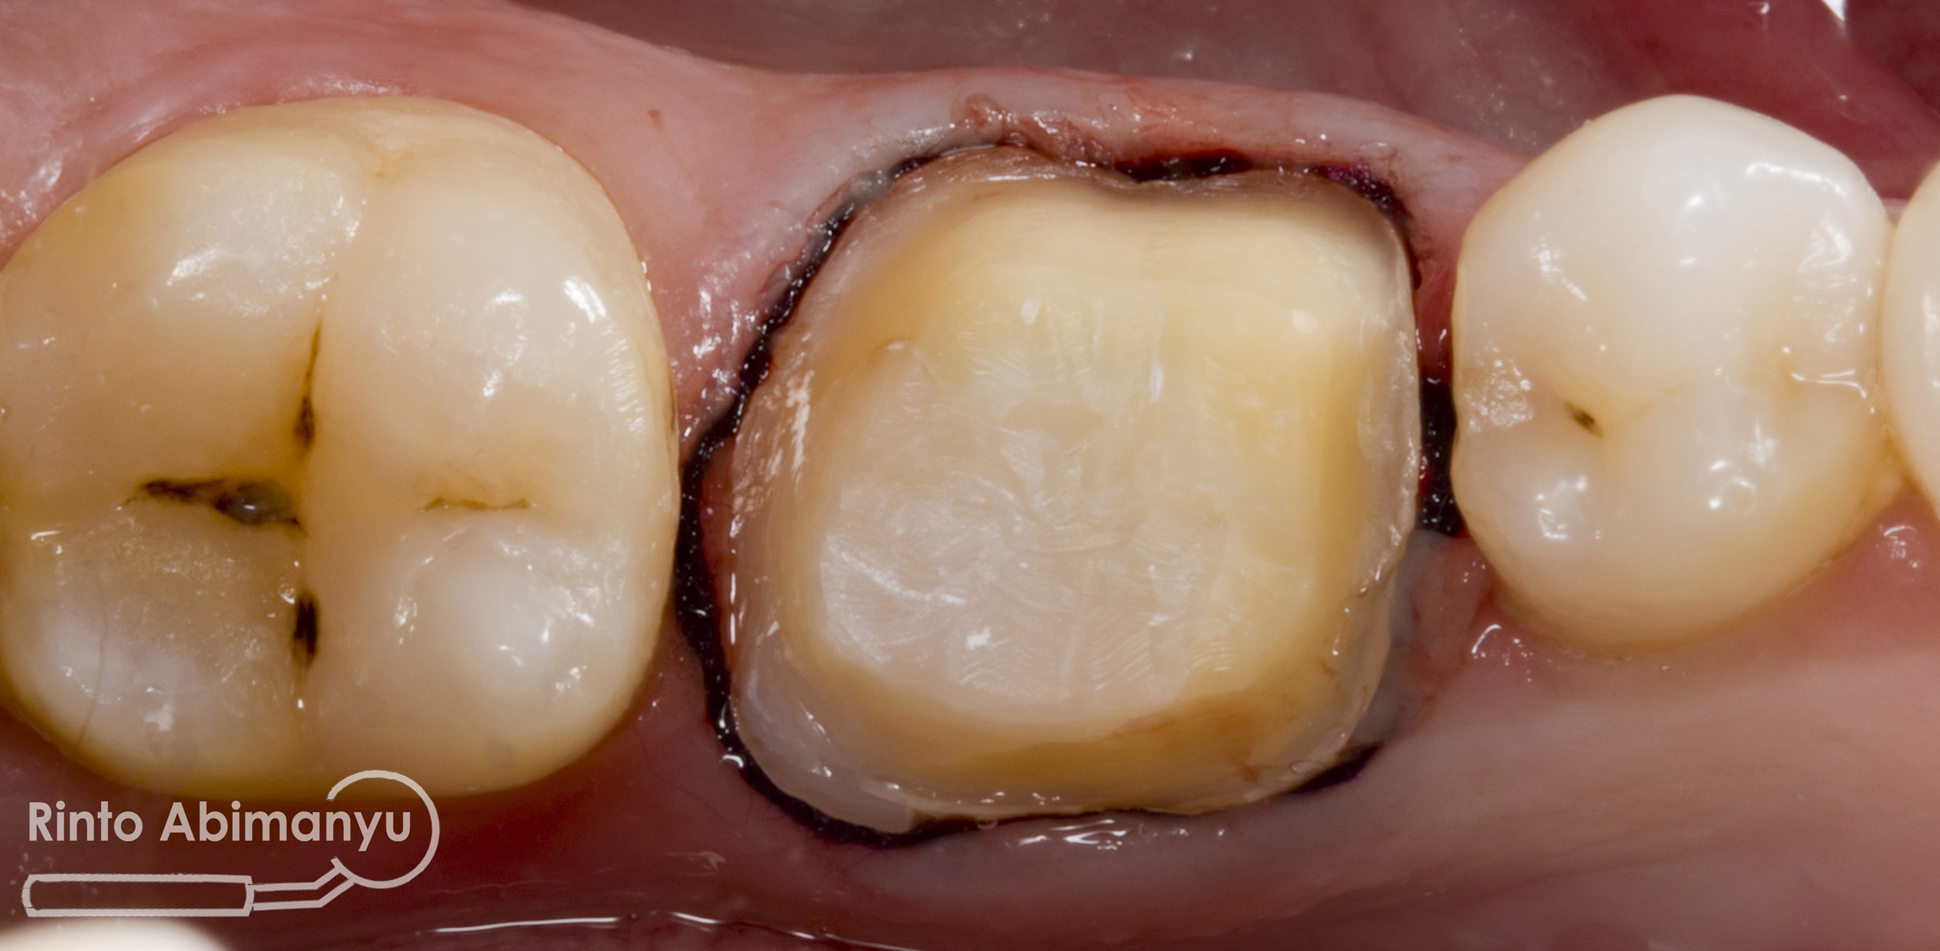

Setalah itu gigi dipreparasi dengan akhiran tepi preparasi chamfer, preparasi kemudian dihaluskan menggunakan arkansas stone dan juga rubber point… Sebelum pencetakan, sulkus gingiva diselipkan retraction cord ukuran #000 yang sebelumnya telah dicelupkan di larutan aluminum chloride 25%…

Setelah selesai pencetakan gigi dibuatkan crown sementara menggunakan cetakan yang telah dibuat sebelum preparasi, cetakan tersebut diisi dengan bahan crown sementara self cured composite dan dimasukkan ke gigi yang selesai dipreparasi.. Kurang lebih 3 menit lalu cetakan diangkat dari gigi dan didalam cetakan sudah terbentuk crown sementara dilanjutkan dengan trimming untuk membuang kelebihan bahannya… Crown sementara disemenkan ke gigi memakai Freegenol (GC)…